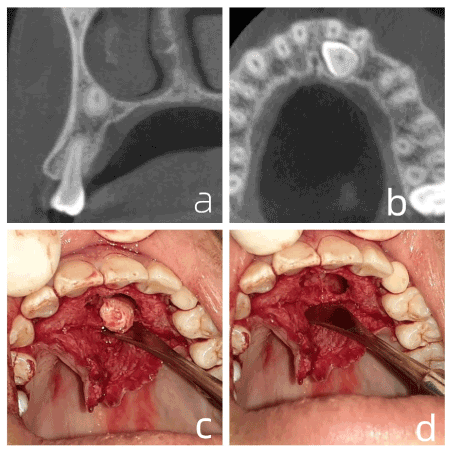

A male patient, dark-skinned, 16 years old, was referred to the Maxillofacial Anatomy and Traumatology League (LATIUM) of the Federal University of Ceará - Sobral Campus (UFC) for extraction of an included tooth (23). The included tooth was initially visualized using panoramic radiography, performed for orthodontic study. However, its vestibule-palatine positioning remained elusive, and cone beam computed tomography (CBCT) was requested. When evaluating the CBCT exam in detail, the proximity of the root apex to the nasal fossa was observed, parallel to the para-sagittal cut in the region of tooth 24 (Figure 1a), an axial cut in the region of the crown of tooth 23 (Figure 1b) its location near the palate, and the intimate contact of this crown with the roots of teeth 21 and 22, were all observed; requiring careful care in the region. Anesthesia was performed at the bottom of the buccal groove in the region of tooth 24 to anesthetize the tooth 23 nerve bundle, and, in addition anesthetizing the incisive foramen region of the palate in order to reach the mucosa of the region. The envelope incision, with a #15 blade, involved the entire palatal groove from the mesial of tooth 14 to the mesial of tooth 24. Osteotomy with a #6 spherical drill was performed at high rotation to expose the crown of tooth 23, (being in close contact with tooth 21), which was followed by a high-rotation odontosection with a #703 tapered cone drill to preserve maxillary bone. Figure 1c presents removal of the last fragment after the odontosections, managing to preserve the thin layer of bone that separated the crown of tooth 23 from the roots of teeth 21 and 22. After extraction, osteoplasty and abundant irrigation with saline were performed (Figure 1d), followed by transpapillary suture of all anterior teeth.

Figure 1. a. parasagittal section showing the location of the root apex of 23. b. axial section showing the position of the crown of the tooth 23. c. last fragment removed. d. surgical surface after osteoplasty and abundant irrigation

Thus, the requests for tomographic examinations in cases 1 and 2 are justified, as they allow better visualization of the region to be operated, as well as a safer and more comfortable surgery for the patient. In case 1, we mention visualization of the root apex of tooth 23, located in the tooth 24 root apex region, which enabled more effective anesthesia through a puncture point located at the bottom of the buccal groove of the apex of tooth 24.

Citing case 1, we can see intimate contact between the crown of tooth 23 and the root of tooth 21. Our surgery avoided wear in the region close to the buccal region of tooth 23 and damaging the root of tooth 21.